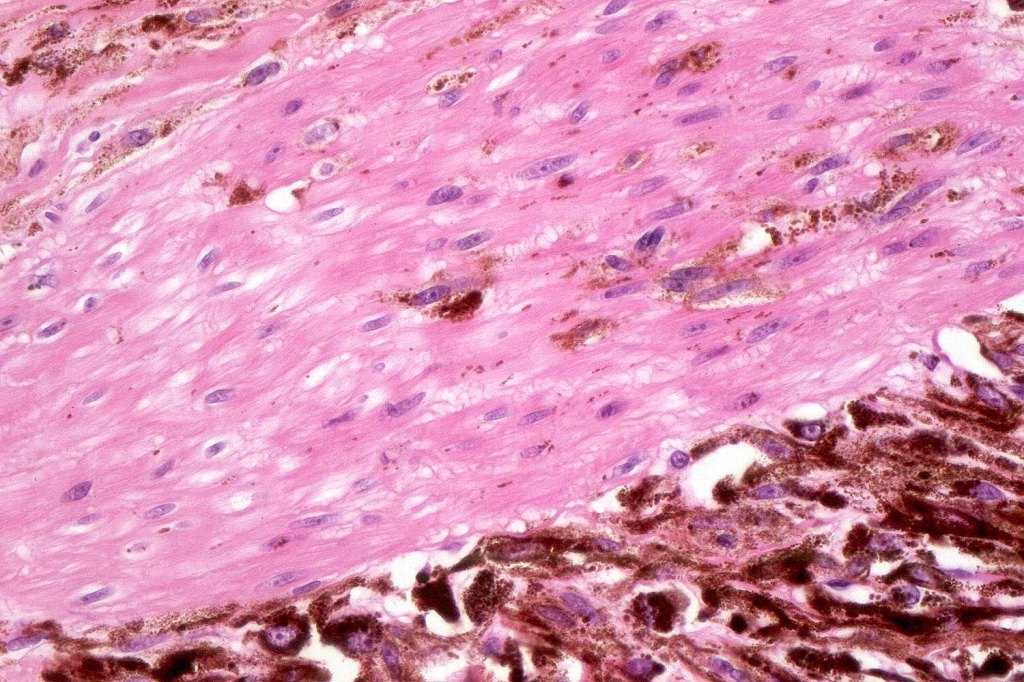

•Cytoplasm is pale and nuclei are small with inconspicuous nucleoli

•Mitoses are typically very sparse or absent

•No atypical mitoses

•No Necrosis or lymphovascular invasion